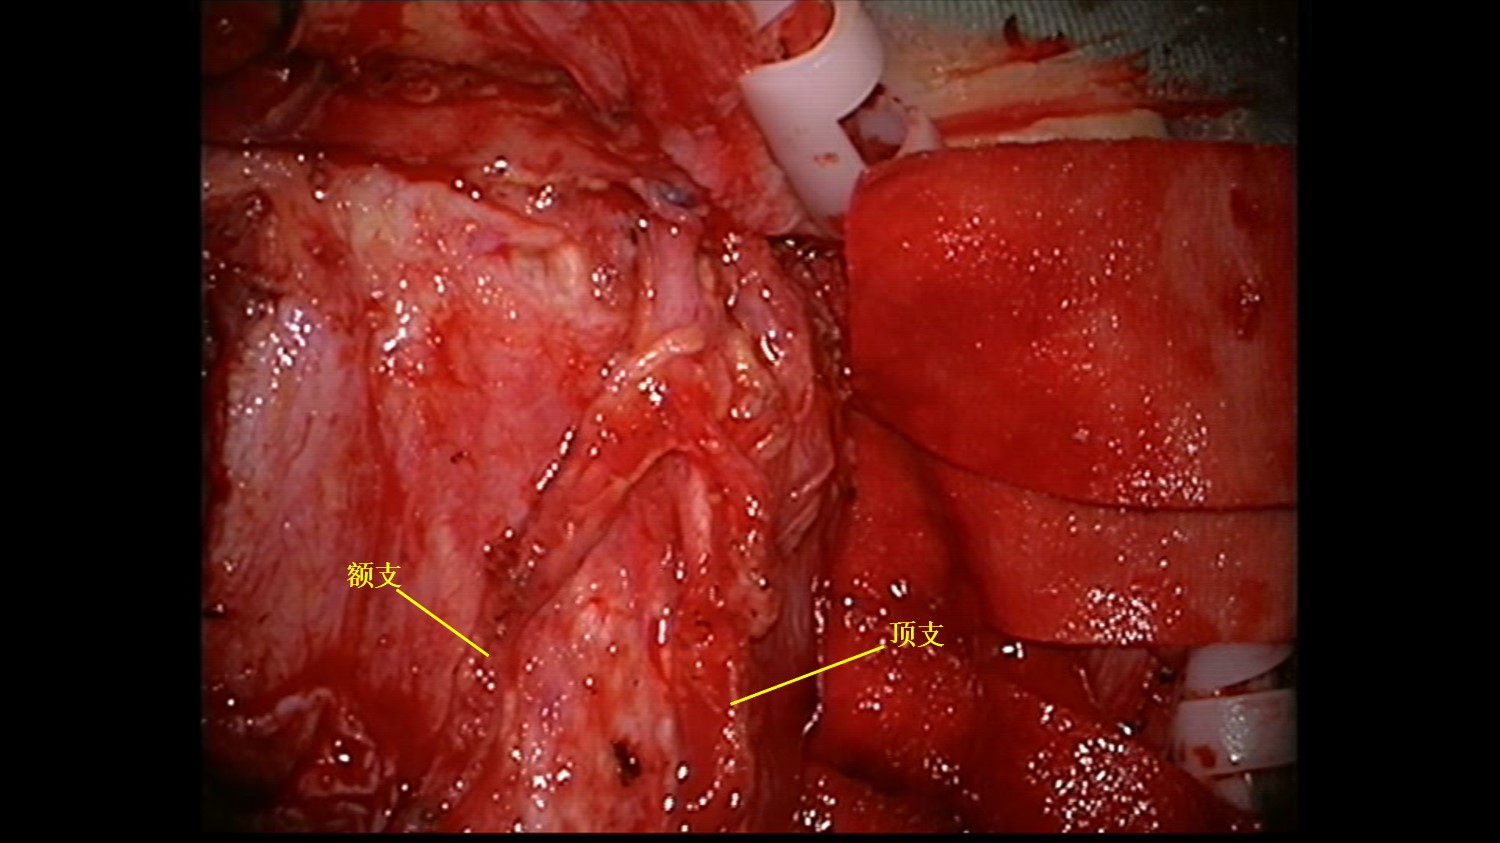

术中分离STA额支、顶支